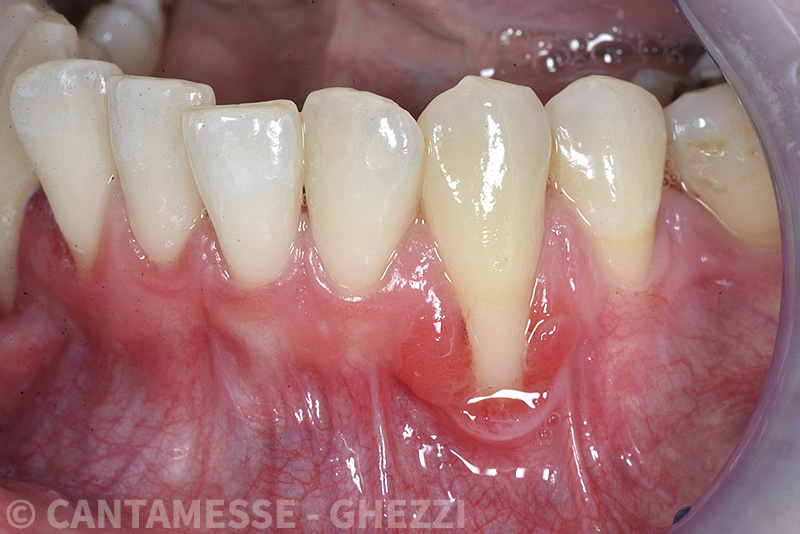

PREMESSA: in seguito all’estrazione dell’incisivo laterale superiore di destra, resasi necessaria per cause batteriche, si decide di affrontare il caso con il posizionamento di un impianto in sostituzione dell’elemento mancante dopo guarigione del sito infetto. Con tecniche rigenerative sia dei tessuti ossei mancanti a causa dell’infezione pregressa, sia dei tessuti gengivali che appaiono inizialmente troppo spostati in alto, si ripristina una corretta morfologia delle parabole (contorni) gengivali e delle papille interdentali (triangoli di gengiva tra due denti vicini).

Vengono utilizzati 2 tipi di provvisori: il primo, cementato ai denti vicini, viene utilizzato dal momento dell’estrazione del dente fino ad impianto osteointegrato (circa 6 mesi); il secondo, avvitato direttamente all’impianto, ha una funzione di prova estetica ma soprattutto di guida per la maturazione dei tessuti gengivali peri-implantari portandoli verso la maturazione completa prima di posizionare la corona finale in disilicato di litio.